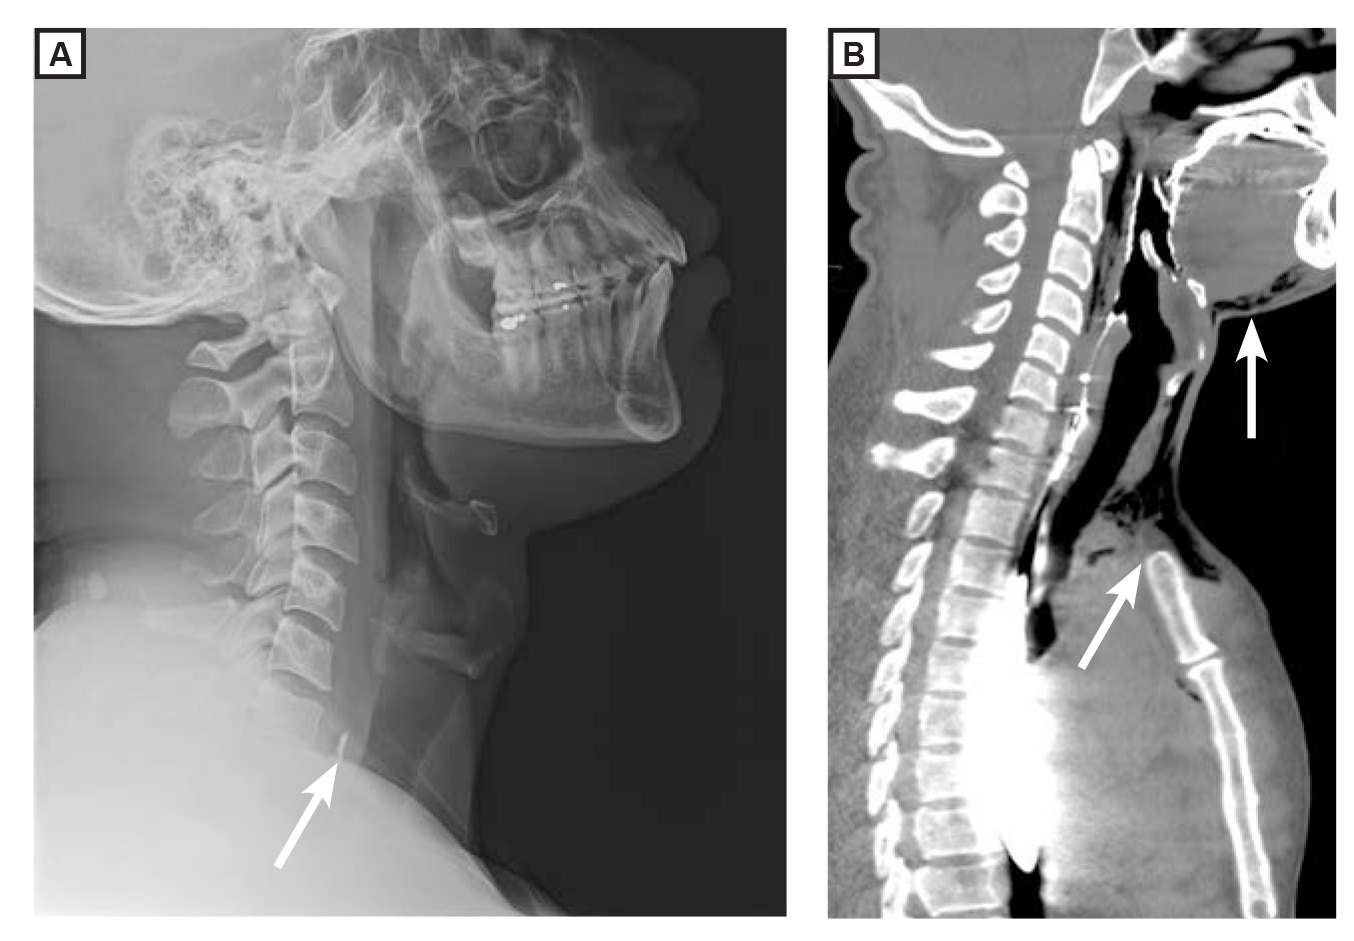

A 33-year-old man presented to the emergency department with odynophagia 2 days after eating chicken wings. A radiographic image of the cervical spine from a lateral view revealed a 1.4-cm linear radiopaque foreign body overlying the esophagus at T1 (image A, arrow). An esophagogastroduodenoscopy showed a 3-cm chicken bone lodged horizontally at the upper esophageal sphincter. After multiple unsuccessful attempts to remove the foreign body with forceps, a ridged esophagoscopy with endoscopic scissors was used to transect and remove the bone. Physical examination of the patient’s neck the day after the removal revealed soft tissue crepitus. A computed tomographic scan showed subcutaneous emphysema in the anterior neck and mediastinum (image B, arrows), indicating esophageal perforation. Because he lacked systemic symptoms, the patient was treated conservatively with antibiotics and intravenous fluids. He showed no signs of sepsis 72 hours after treatment and required no surgical intervention.